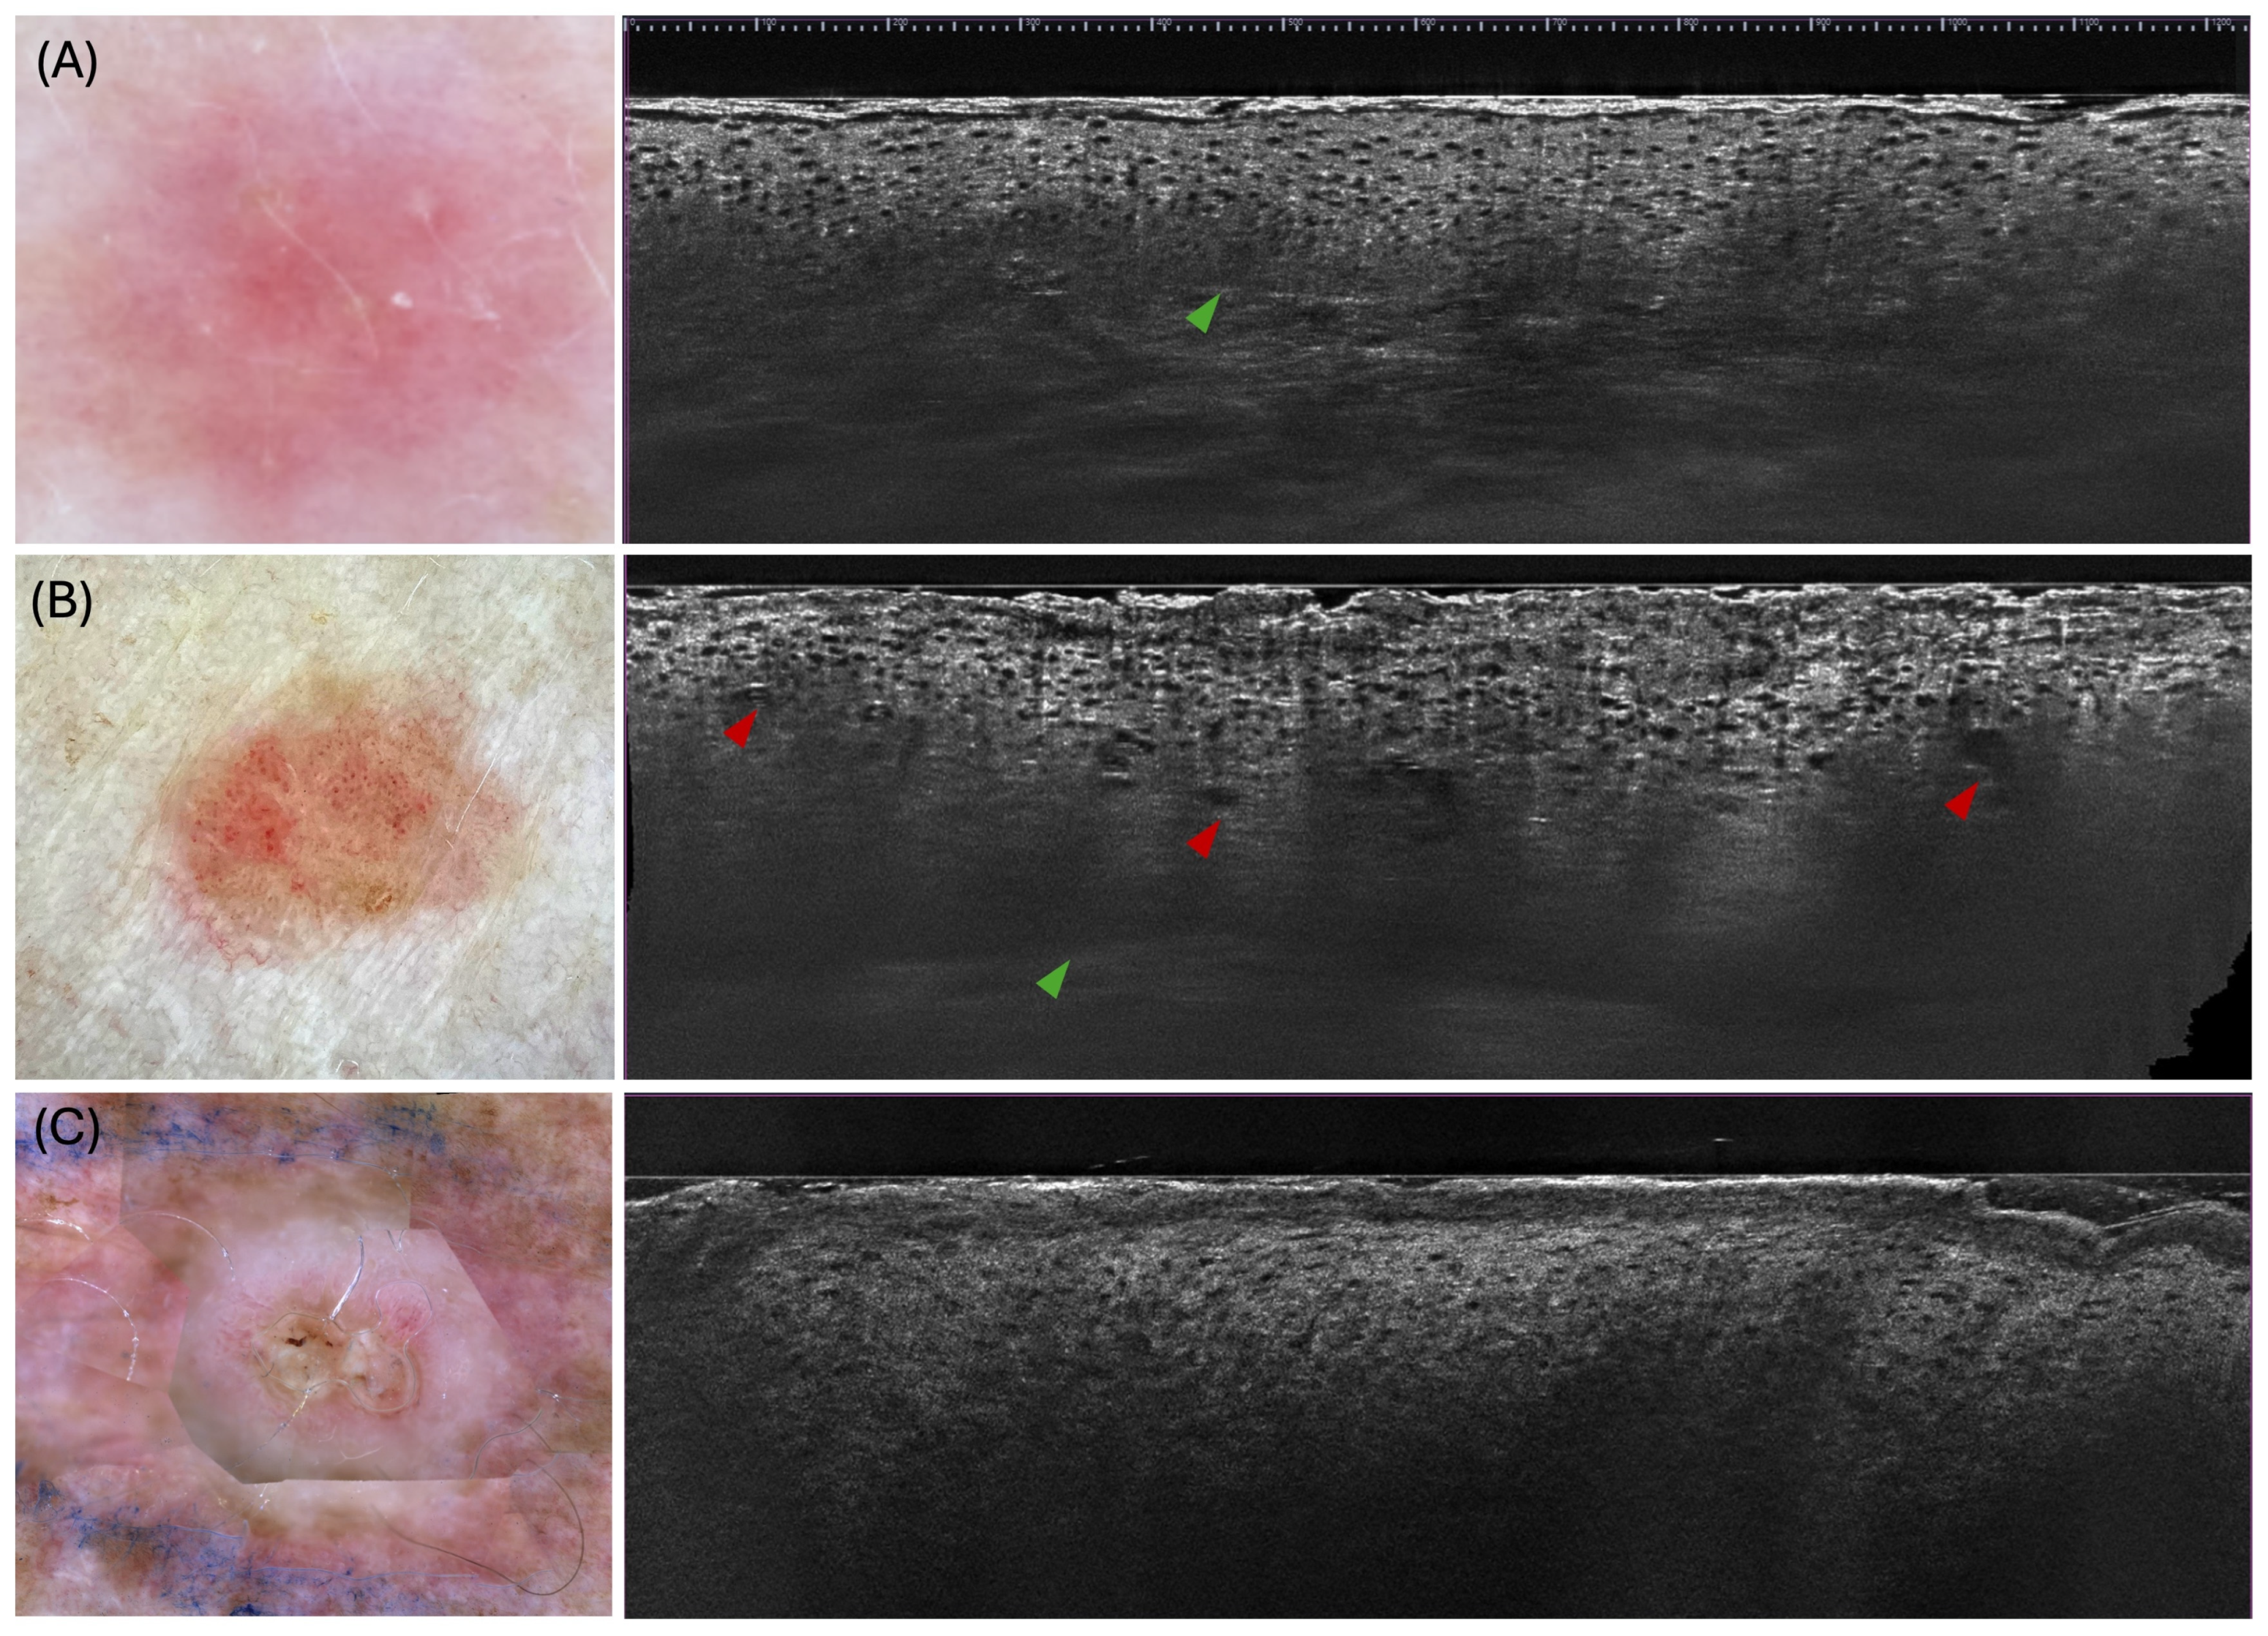

3.1.1. Actinic Keratosis

3.1.2. Bowen’s Disease

3.1.3. Invasive Squamous Cell Carcinoma

| Actinic keratosis | [28,30,31,32,33,34,35,36,37,38] | Hyperkeratosis (42–100%) Parakeratosis (64–83%) Acanthosis (71–76%) Keratinocytic atypia (82–100%) | Mean epidermal thickness 105–126.2 μm Well-preserved/visible DEJ (48–70%) Architectural disorganisation (77.8–97%) Tumour budding (45–58%) | Dilated vessels (57.1–89.5%) Elastosis/collagen alterations (26.2–61%) |

| Bowen’s Disease | [32,35,36] | Hyperkeratosis (69.4–100%) Parakeratosis (63–100%) Keratinocytic atypia (73.3–100%) | Mean epidermal thickness 141–168.5 μm DEJ well-defined (24–80%), Bowenoid pattern (90%) Architectural disorganisation (>90%) Tumour budding (33.3–49%) Broad strands (9.7%) | Dilated vessels (44–70%) Glomerular vessels (20–61.9%) Elastosis/collagen alterations (10–70%) |

| Invasive SCC | [30,32,35,36,37,38,39] | Hyperkeratosis (72.7–100%) Parakeratosis (62–93.8%) Acanthosis (75–93.8%) Marked keratinocytic atypia (70–84%) Atypical nuclei (95%) Erosion/ulceration (63–68%) | Mean epidermal thickness 154–232 μm DEJ well-defined (18.8–57%) Architectural disorganisation (93–100%) Tumour budding (44–45%) Broad strands (29–63%) | Dilated vessels (55–78.6%) Glomerular vessels (21.4–80%) Elastosis/collagen alterations (7.4–75%) Keratin pearls (0–81%) |